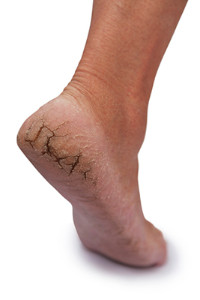

Many people who enjoy walking barefoot or wearing flip-flops during the summer months may be surprised to learn that there may be consequences that can follow as a result of this. The skin may become dry, calluses may possibly form, and fissures in the skin of the heels, known as cracked heels, may develop. If the cracks in the skin should bleed, severe pain, discomfort, and infection may accompany this condition. There may be remedies that can be practiced to prevent and relieve extremely dry skin, and these may include washing and drying the feet thoroughly followed by utilizing a good moisturizer. At this point, it is suggested to wear socks while sleeping for the night, and this may aid in healing painful fissures. If you would like additional information about how to treat cracked heels, it is advised to consult with a podiatrist who can discuss the best options for you.

If the skin on your feet starts to crack, you may want to see a podiatrist to find treatment. If you have any concerns, contact Brent Harwood, DPM from Southeast Podiatry. Our doctor can provide the care you need to keep you pain-free and on your feet.

Cracked Heels

It is important to moisturize your cracked heels in order to prevent pain, bleeding, and infection. The reason cracked heels form is because the skin on the foot is too dry to support the immense pressure placed on them. When the foot expands, the dry skin on the foot begins to split.